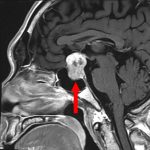

712

'25年12月

70代

下垂体腫瘍

頭蓋内腫瘍摘出術

No.’25_114 手術前1